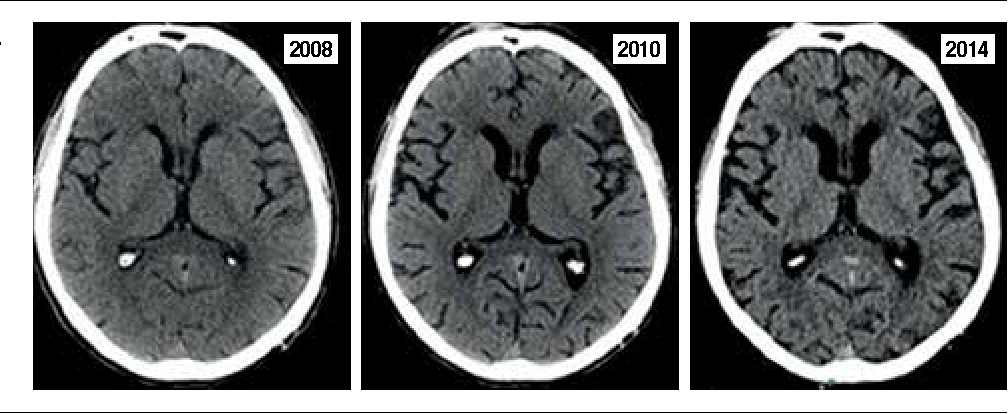

По мере того, как умирает все больше и больше клеток, мозг сокращается (атрофируется) и симптомы обостряются. Какие симптомы проявятся первыми, зависит от того, какая часть головного мозга атрофируется, поэтому на людей воздействуют по-разному.

Эти бляшки и клубки повреждают нервные клетки, что приводит к их гибели и сокращению мозга, как показано выше.

Следовательно, сосудистая деменция может прогрессировать постепенно, как БА, или, если она вызвана инсультом, ступенчато, с ухудшением симптомов после каждого инсульта.